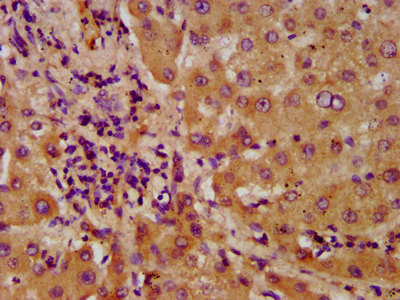

IHC image of CSB-PA891535LA01HU diluted at 1:600 and staining in paraffin-embedded human liver tissue performed on a Leica BondTM system. After dewaxing and hydration, antigen retrieval was mediated by high pressure in a citrate buffer (pH 6.0). Section was blocked with 10% normal goat serum 30min at RT. Then primary antibody (1% BSA) was incubated at 4°C overnight. The primary is detected by a biotinylated secondary antibody and visualized using an HRP conjugated SP system.

IHC image of CSB-PA891535LA01HU diluted at 1:600 and staining in paraffin-embedded human liver cancer performed on a Leica BondTM system. After dewaxing and hydration, antigen retrieval was mediated by high pressure in a citrate buffer (pH 6.0). Section was blocked with 10% normal goat serum 30min at RT. Then primary antibody (1% BSA) was incubated at 4°C overnight. The primary is detected by a biotinylated secondary antibody and visualized using an HRP conjugated SP system.